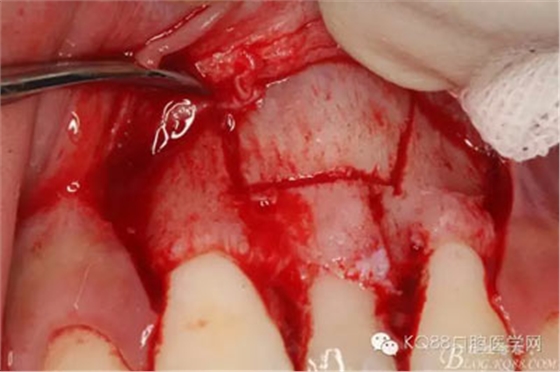

圖10.形成梯形骨縫

圖11.掀開骨壁。摘除牙瘤及牙囊組織

圖12.摘除囊壁后,暴露出21的切端